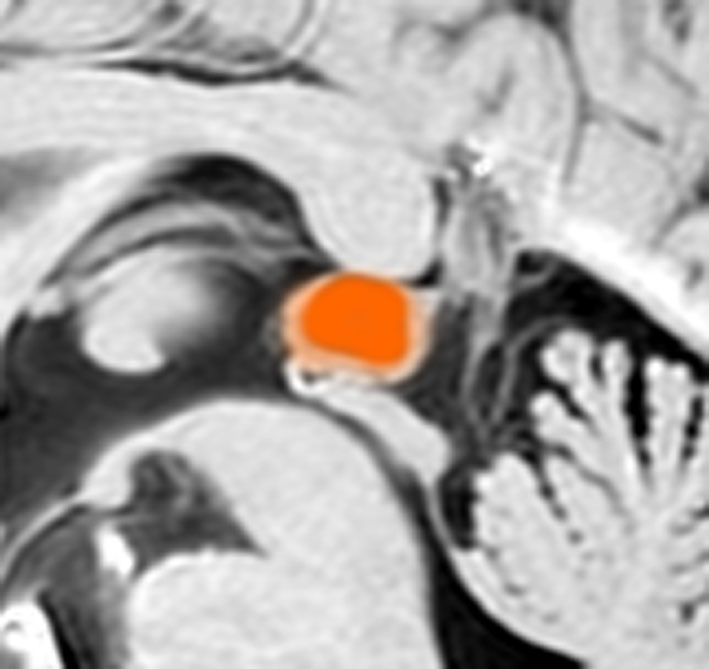

20年間経過観察されている松果体のう胞です。ガドリニウム増強で周囲が白く増強されているのですが,これはのう胞壁ではなく静脈です。

松果体のう胞の経過観察にはガドリニウム増強する必要はないし,そもそも中濃水道橋策がないものでは数年もみれば十分なものです。